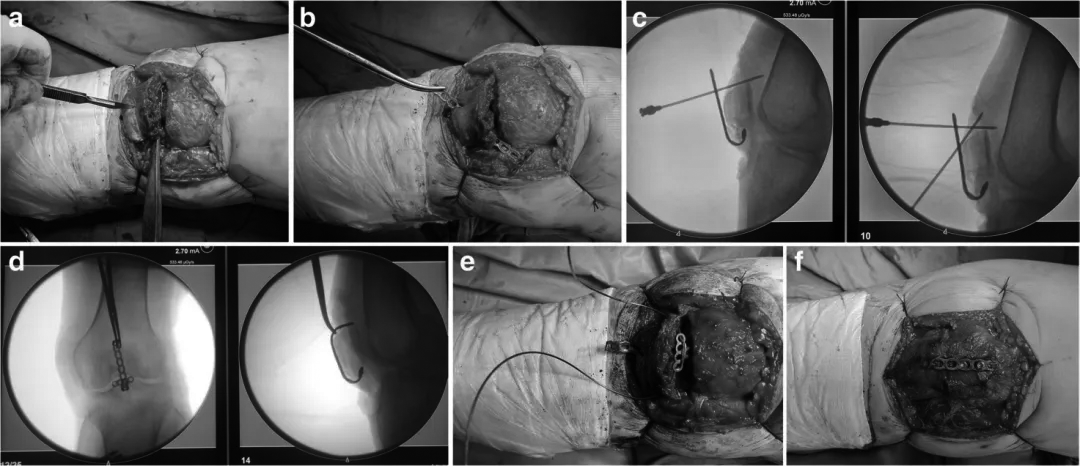

在我们的研究中,用于固定的锚状钢板是通过折弯t形钢板制成的(图1)。麻醉满意后,将患者置于仰卧位,预防性使用抗生素,并在大腿近端放置止血带。经膝关节中线纵行切口打开皮瓣,暴露骨折,清除骨折断端血凝块。术中避免剥离髌前筋膜和骨膜,防止骨折块分离。确定骨折类型及移位程度。

然后在髌腱表面用刀连接髌骨下极做一个小开口,t形钢板通过这个小开口穿过髌腱,将钢板的t形端牢固地固定在下极骨折块表面(图1a -b)。此时髌腱向钢板被牵拉的方向移动。在此手术中,我们不仅治疗下极骨折,而且还抵消了髌腱对下极骨折块的牵拉作用。钢板t形端部的宽度必须大于远端骨折块的宽度,以防止骨折块从钢板边缘穿透。术中需进一步塑形钢板角度,使钢板贴近髌骨表面,钢板位置需保证t形端部贴近下极骨折块表面(图2 -d);另一端靠近髌骨上极表面(钢板切至合适长度)。然后将直径1.0mm的钛缆或钢丝穿过钢板的t端,借助腰椎穿形针通过髌骨周围的软组织交替进行环扎固定(图2e)。环扎固定后,钛缆或钢丝拧紧加压,钢板依次用螺钉固定于髌骨表面。

所有螺钉均为2.7个系统螺钉。一般我们建议垂直于髌骨上表面的螺钉为皮质螺钉,其余为锁头螺钉;所有螺钉均采用单皮质固定(图2f)。采用c型臂透视评估骨折复位情况;屈曲膝关节,观察骨折块固定的稳定性。确认骨折固定满意后,在创面保留引流管,逐层闭合创面。

图2. 定制锚钉式钢板治疗髌骨下极骨折术中情况。

a.用手术刀在下极的髌腱处切开一个小口。

b钢板穿过髌腱小切口。

c-d术中钢板进一步塑形。

e组合钢丝的附加环扎。

f抱箍加压后,依次用螺丝固定。